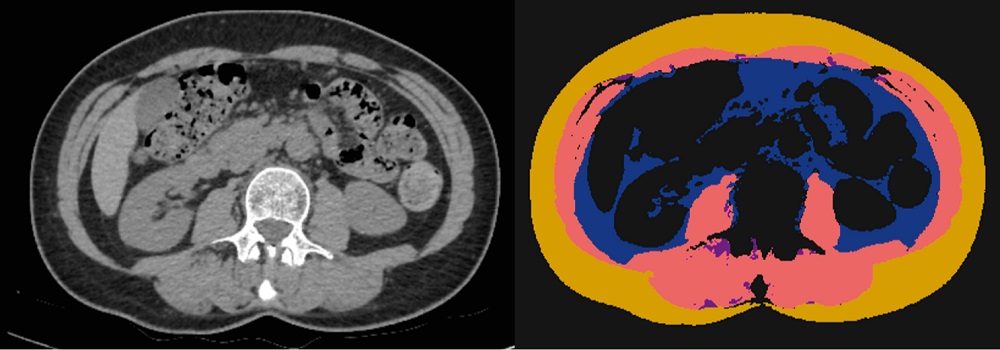

КТ ОБП для каждого включенного в исследование пациента анонимизированы и обработаны с использованием ранее разработанного ПО на основе ТИИ. Для обработки использовались единичные срезы на уровне середины тела L3 позвонка. Корректность автоматической разметки оценивалась одним врачом-рентгенологом со стажем работы по специальности 3 года. Дополнительно рассчитаны 1 нормализованный и 1 относительный параметры – скелетно-мышечный индекс (СМИ) и доля внутримышечного жира. Пример сегментации алгоритмом КТ изображения на уровне L3 позвонка и автоматически определяемые параметры жировой и мышечной ткани представлены на рис. 2 и в табл. 1.

Рис. 2. Пример автоматической сегментации КТ-изображения, выполненной программным обеспечением на основе технологий искусственного интеллекта

Примечание: слева – аксиальный срез на уровне середины тела L3 позвонка в нативной фазе сканирования. Справа – маски автоматической сегментации: розовым – скелетная мышечная ткань (SMA), желтым – подкожная жировая ткань (SFA), синим – висцеральная жировая ткань (VFA), фиолетовым – внутримышечная жировая ткань (IFA). Описание сегментированных областей представлено в табл. 1. Составлено авторами.

Первый сверточный слой модифицировался для соответствия 2-канальному входу. Пропускные соединения были дополнены адаптерными блоками ResNeXt, что позволяло улучшить качество сегментации в сложных случаях. По результату работы алгоритма создавались PNG-изображения с масками сегментации для скелетной мышечной, подкожной жировой, висцеральной жировой и внутримышечной жировой тканей, а также формировался текстовый отчет со значениями площади данных масок и значением средней рентгеновской плотности скелетной мышечной ткани (рис. 2).